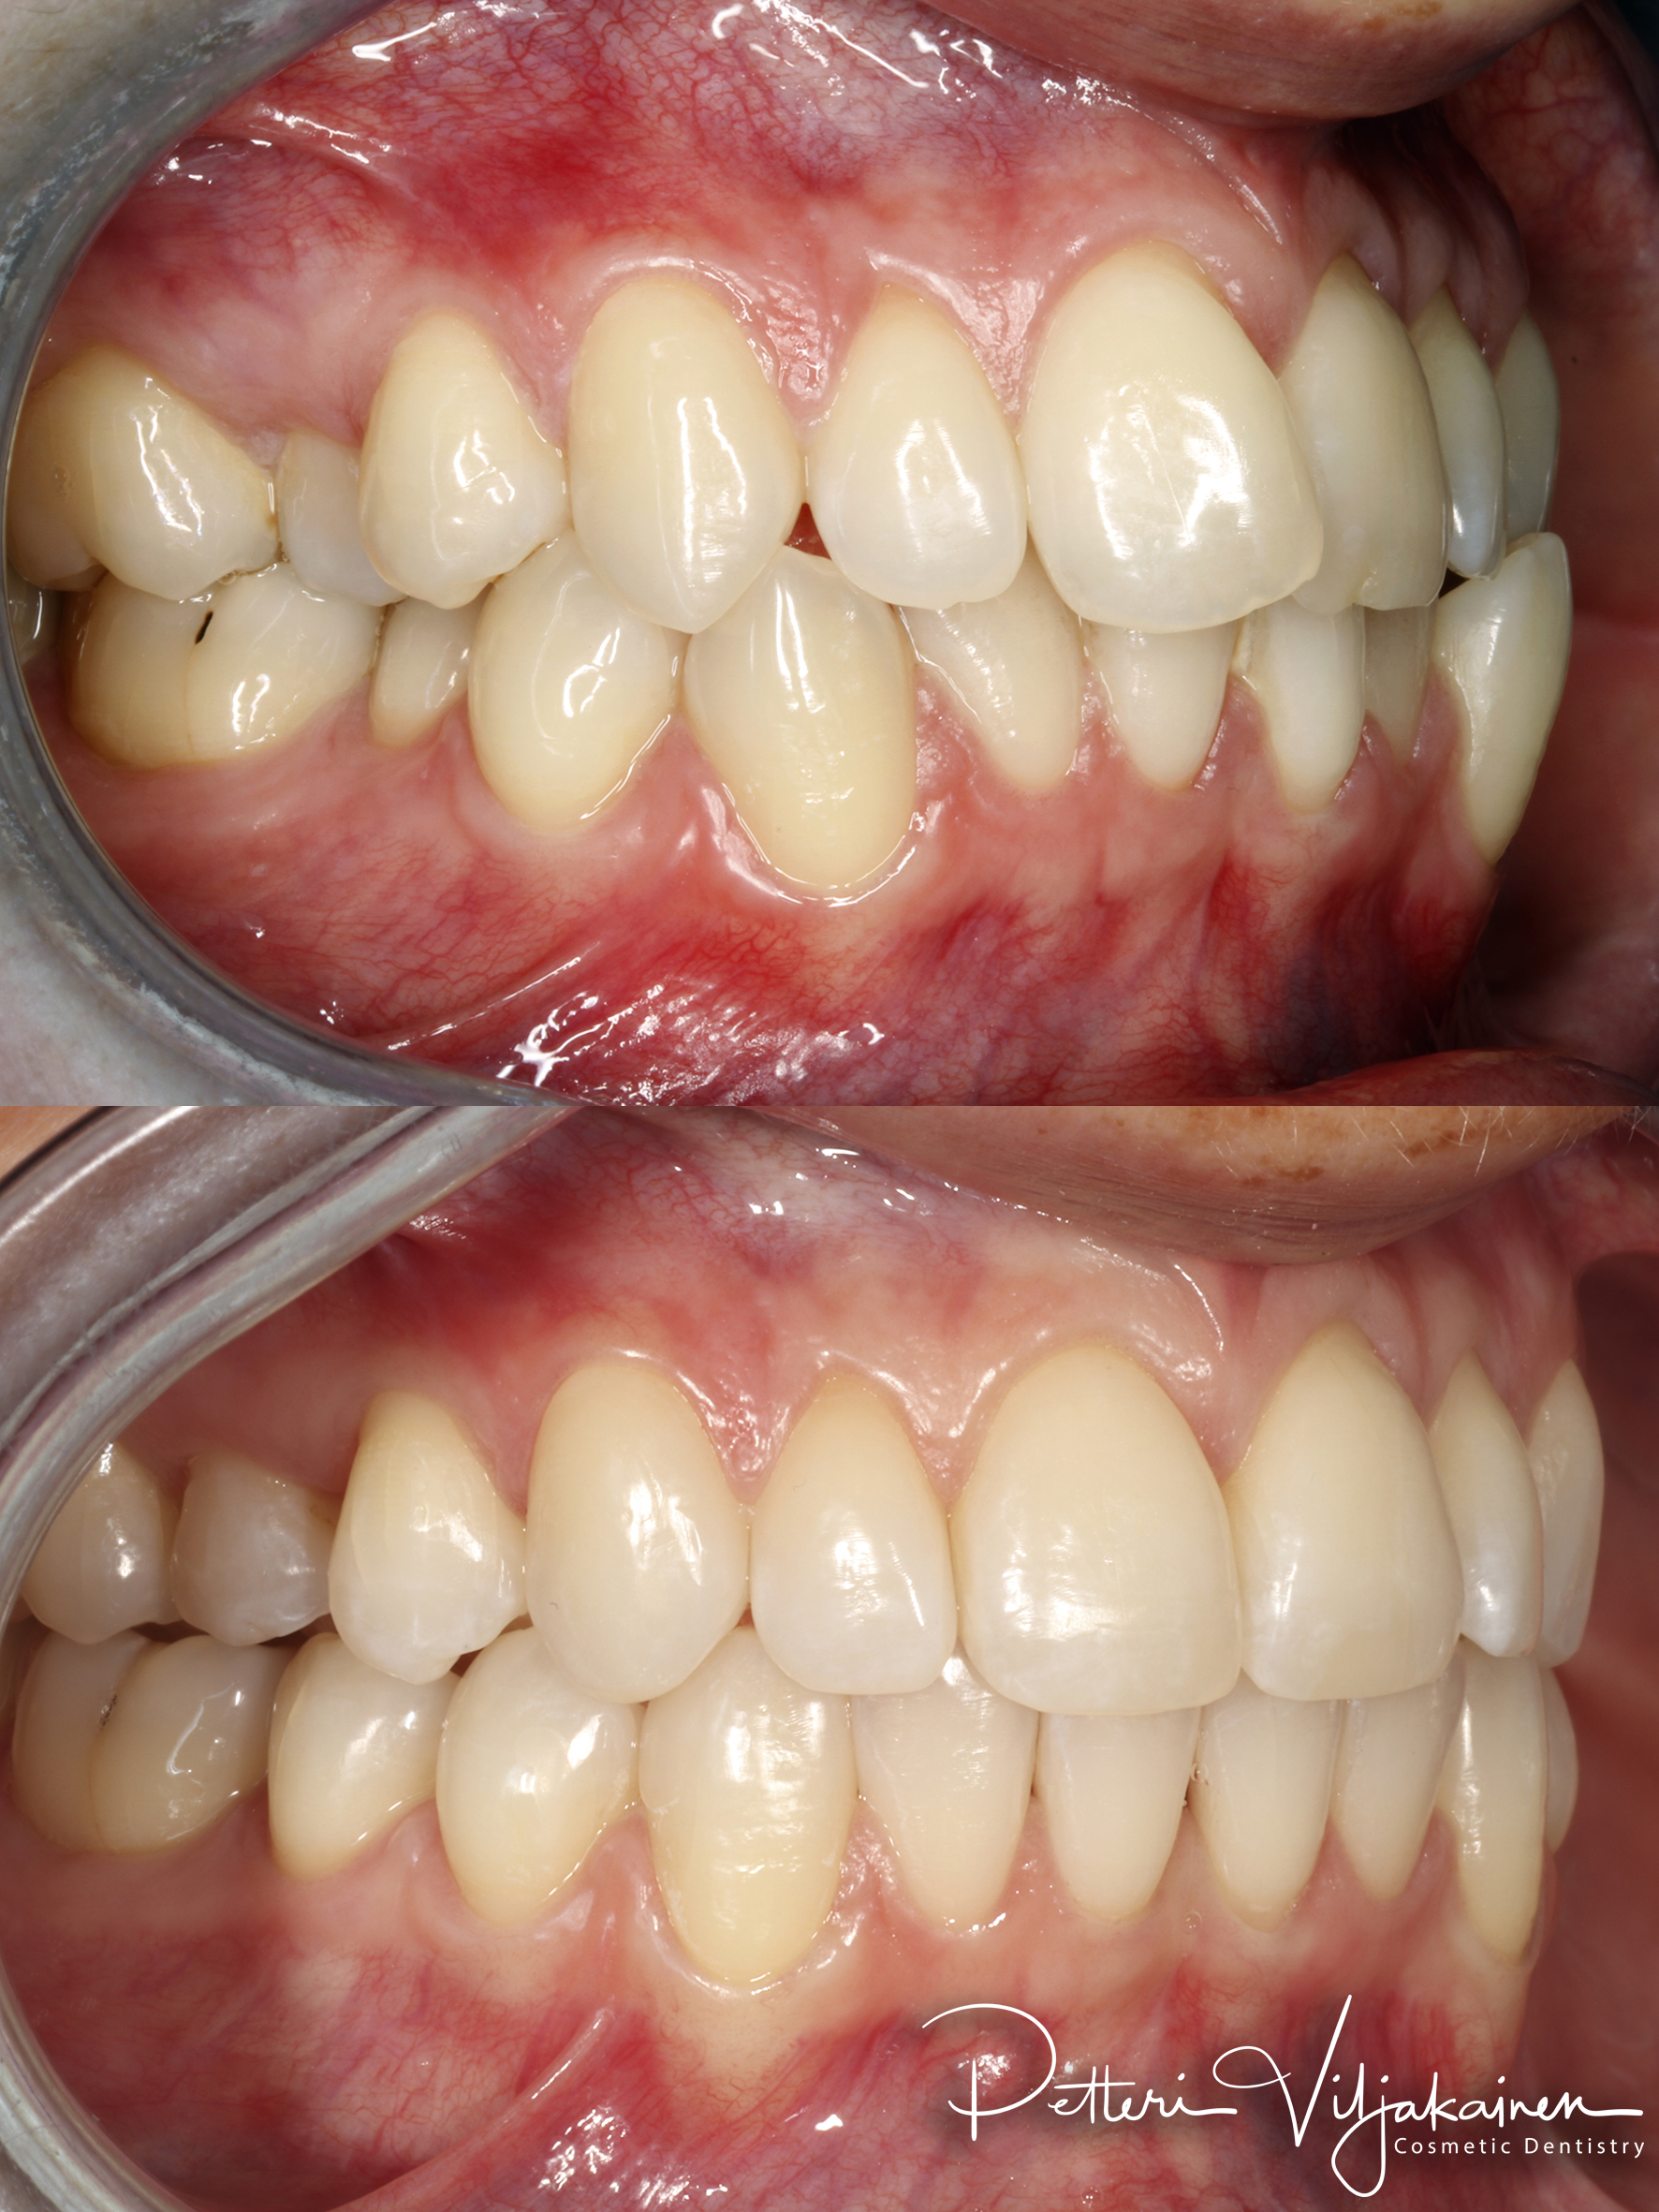

Alla suorittamiani hoitoja ja esimerkkejä siitä minkälaisia purentavirheitä voi korjata.

18kk hoito (Comprehensive). Keraamiset kuoret keskimmäisiin yläetuhampaisiin, kerrostusmuoveilla tehty reunimmaiset yläetuhampaat.